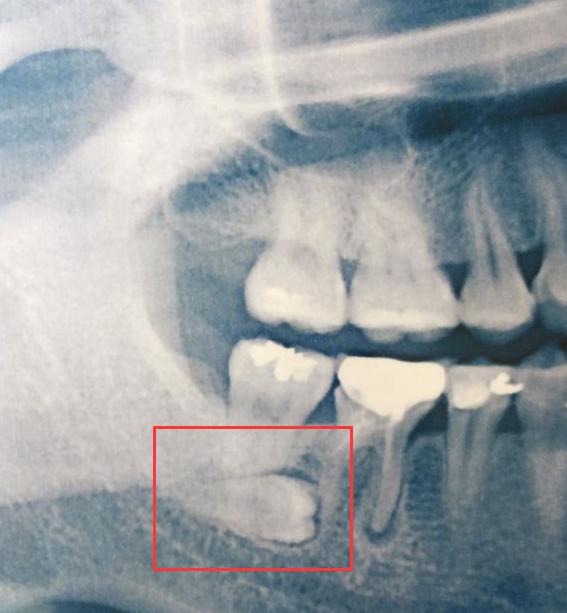

这几天,身边的好几个朋友都去看牙了。他们说 到了医院拍了个X光片,不拍不知道,一拍吓一跳,发现智齿要么躺着长,要么斜着长。

话说,智齿这样长在医学上叫阻生智齿,阻生牙不但会导致牙龈常常发炎,疼痛,还可能会引起邻牙蛀牙,牙根吸收,甚至松动。

高难度智齿

遇到这种智齿就得,拔!!针对那些不知道什么样的智齿该拔的同学,看下面:

3)阻生了,就是被前面牙挡住了,拔